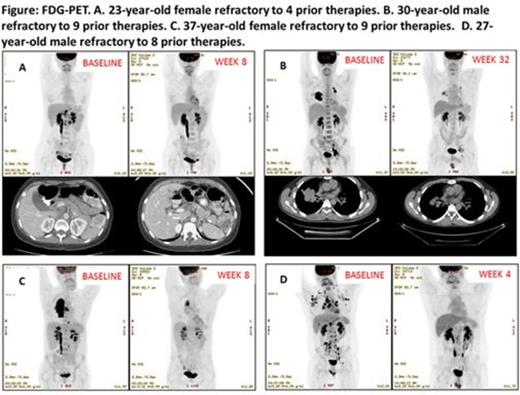

A total of 16 patients (men, n=8; women, n=8), median age 33 years, median of 6.5 prior therapies (including autologous SCT [n=15], autologous and allogeneic SCT [n=4]) were enrolled in dose escalation (n=1) or RP2D (n=15) cohorts. At the median follow-up of 3.2 months, 15 (94%) patients demonstrated decreased FDG uptake including 2 CRs (13%) and 5 PRs (31%) using CHESON criteria, with a total CR+PR rate of 44%. The median reduction of tumor was -27% (-100% to +20%, Figure). The estimated median time-to-treatment failure has not been reached and 63% of the patients continued on therapy with further improvement in their level of disease response. Major grade 3-4 treatment-related toxicities included grade 3 thrombocytopenia (4 patients, 25%), grade 4 thrombocytopenia (6, 38%), grade 3 anemia (1, 6%), febrile neutropenia (1, 6%) and led to treatment interruptions and/or dose modifications in 10 (63%) patients. Five (31%) patients had archival tissue available for targeted next-generation sequencing and one patient had a loss of TSC2, an abnormality that putatively activates mTOR. This patient has had a continuing response to therapy (-56%) for 8.4+ months. PD studies in pre- and post-treatment tumor biopsies, PBMCs and plasma as well as PK analysis continue.